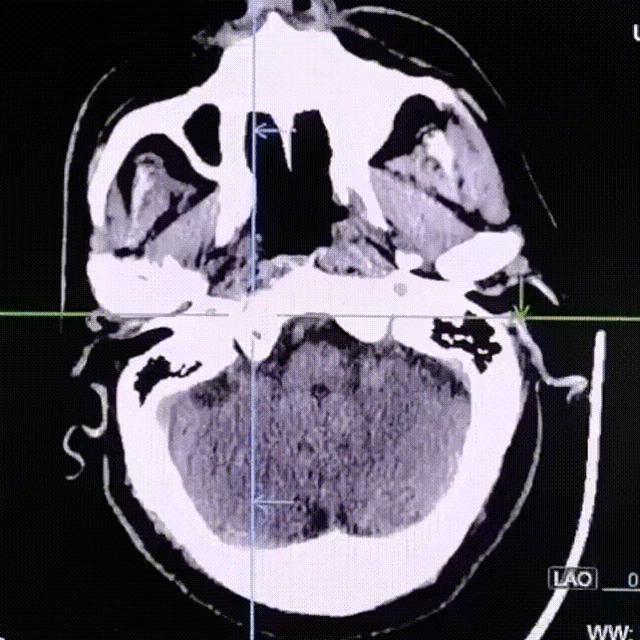

复查CT未见明显颅内血肿和中线移位。术中患者未见明显异常不适,术后拔管缝合、压迫止血,安返病房。

动脉长鞘怎么置入疏堵有道丨8F长鞘辅助BGC球囊导管大脑中动脉取栓术_https://www.jmylbn.com_新闻资讯_第10张

术后CT